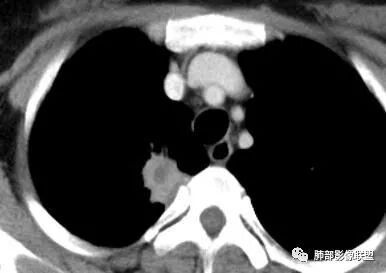

胸部CT:右肺上叶尖段脊柱旁实性结节灶,宽基底与胸膜接触,可见平直征、软毛刺、棘突、空泡,中心片状坏死,周围磨玻璃影边界不清,胸膜增厚、糊墙。增强呈环形强化。右肺下叶实性小结节,见长毛刺、胸膜牵拉。综合考虑:炎性病变,结核可能大。鉴别隐球菌、腺癌。

右肺上叶胸膜下结节,边缘有平直、刀切征及桃尖征,病灶与胸膜呈宽基底,胸膜糊墙,这些征象均指向良性病灶;病灶内可见液化坏死区,壁相对厚,强化较显著;病灶周围较大范围磨玻璃影,边缘模糊,淡薄柔和,未见卫星结节或树丫,提示为一个急性渗出,这是符合炎性病灶脓肿形成的。

换个角度看,右肺上叶这肿瘤符合吗?如此小范围肿瘤灶很少能够在影像上观察到如此明显的坏死,内壁还如此光整?即便是鳞癌,更遑论腺癌及小细胞癌等,不要忘了这是中青年女性患者。

结核易形成空洞,但周围渗出如此明显,没有卫星灶,内壁如此圆整,厚壁强化如此明显,都很难与常见的结核灶关联起来。

会是什么感染?临床症状相对和缓,脓肿单发的,经验上尤以G-杆菌感染较为多见,如肺炎克雷伯杆菌等。